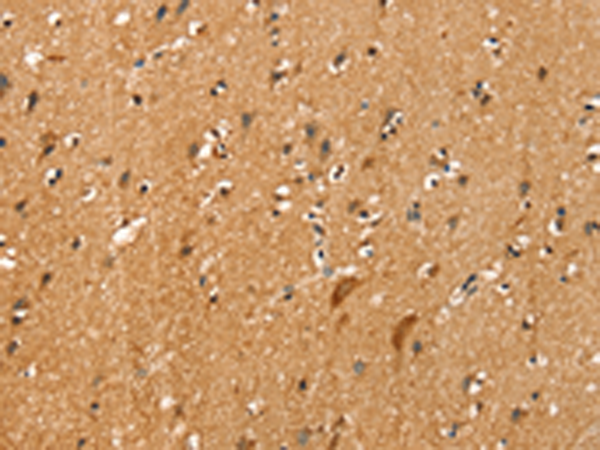

分类: 科研抗体货号: P12181别名: NCKX3应用: IHC反应种属: Human, Mouse, Rat